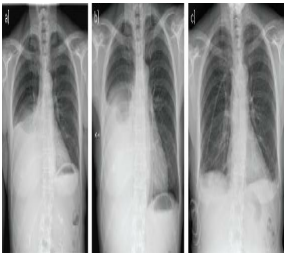

• Flattened diaphragm on chest X-Ray (CXR)

Chest X-ray (CXR)

Fluid in the pleural space,Will gravitate to most dependent area

CXR will showhows pleural effusions, lobar consolidation–> “Patchy infiltrates”